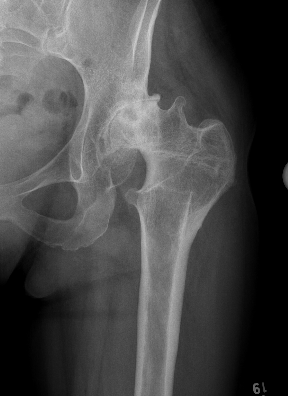

Anatomical issues

| Soft tissues | Acetabulum | Femur | LLD |

|---|---|---|---|

| Sciatic nerve in abnormal position | Shallow | Increased anteversion | Maximum sciatic nerve can be lengthened is 3-4 cm |

| Hamstring / adductors / rectus tight | Anteverted | Valgus neck shaft angle | |

| Horizontal abductors function less efficiently |

Deficient bone stock anteriorly and superiorly |

Short offset | |

| Thick hourglass capsule | Narrow tapered femoral canal with tight isthmus | ||

| Thickened psoas tendon | Posterior displacement of the greater tuberosity |